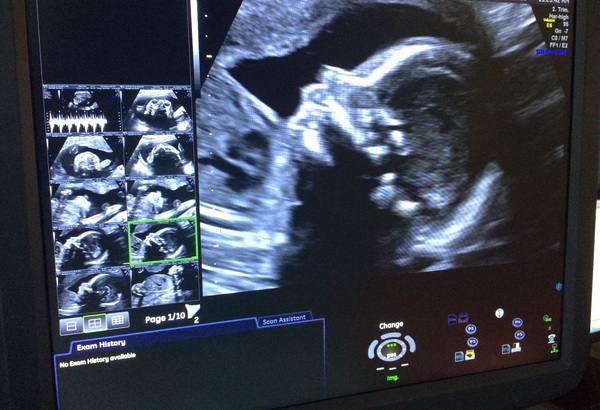

wispaxmas · 23/09/2016 12:51

Everything is a-ok with my baby GIRL! I texted DH to tell him everything was fine midway through the scan, and took loads of photos, but it would have been a bit much to record I think. Especially as most of it is boring measurements!